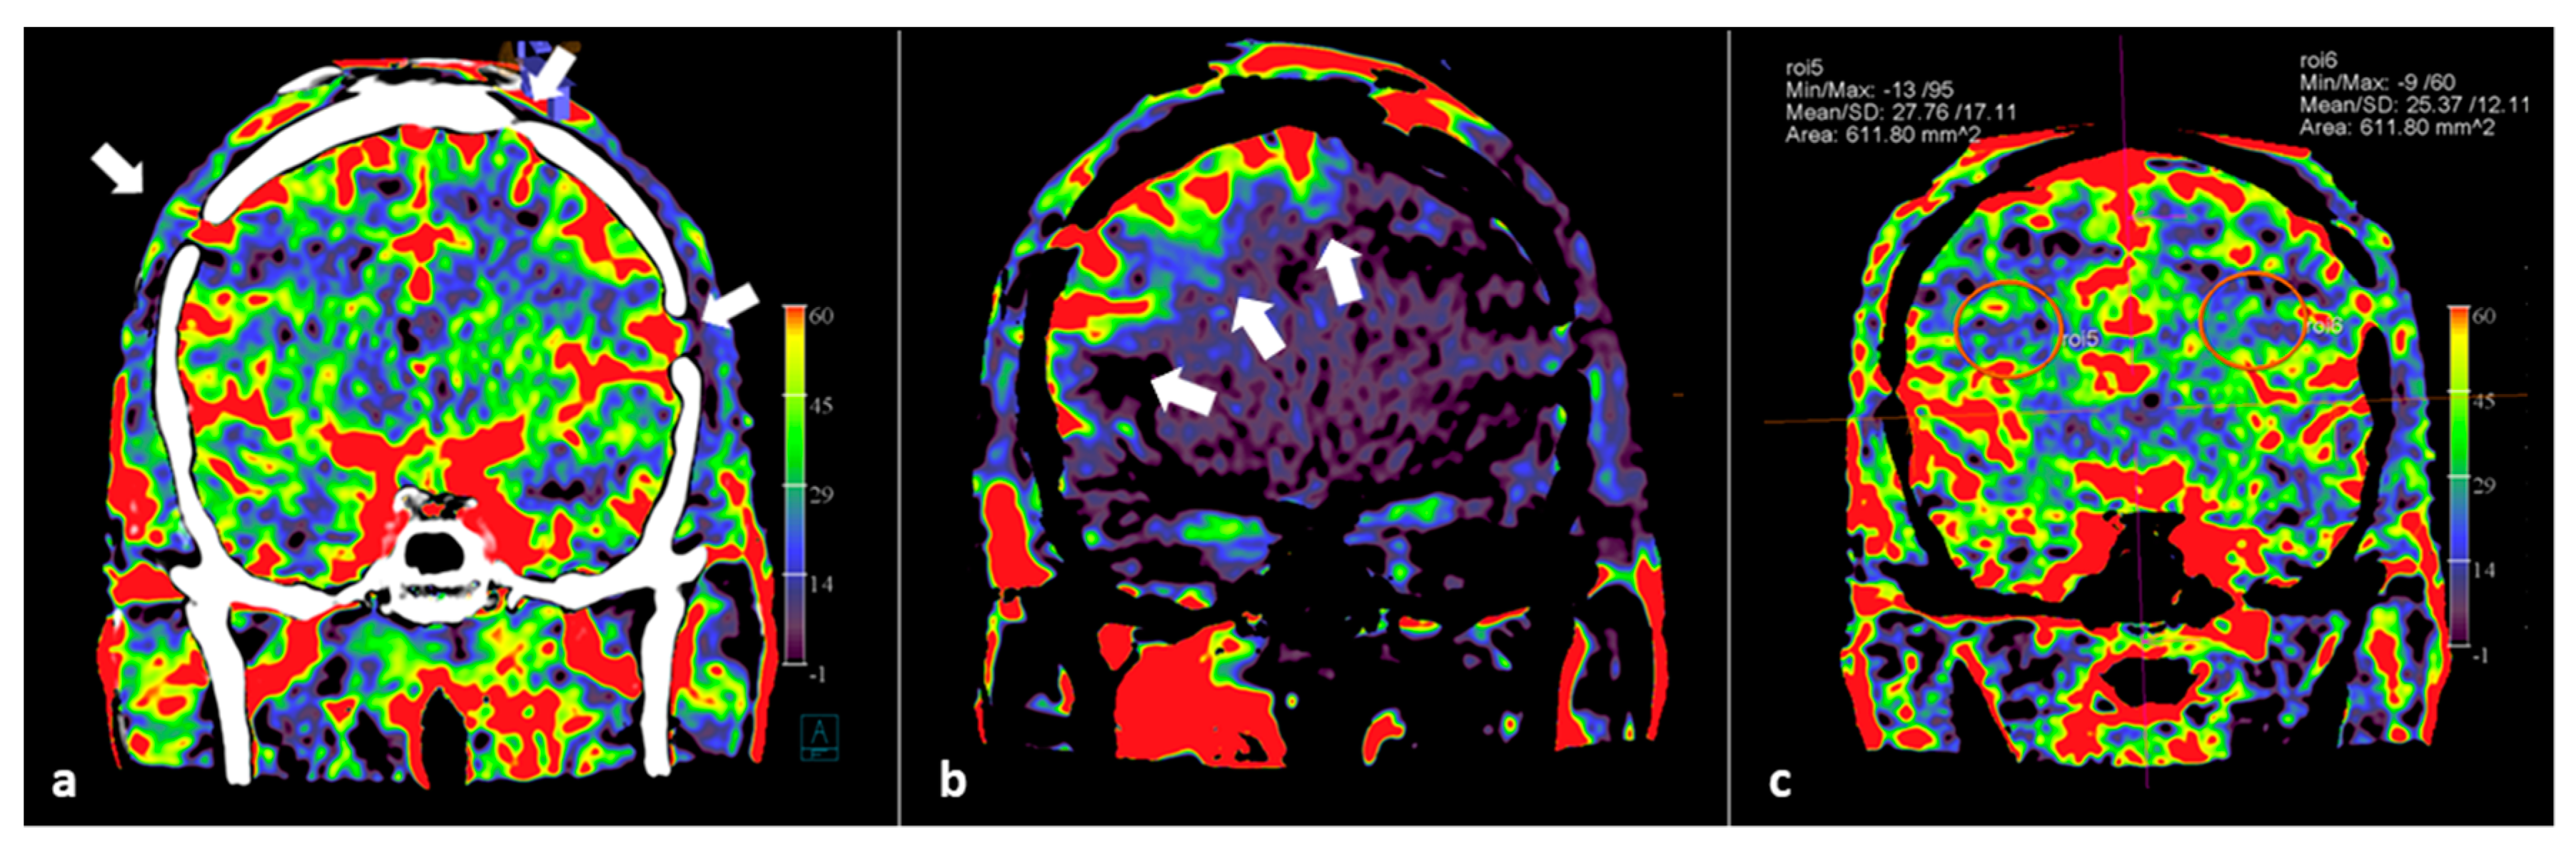

Recently, we documented the value of PBV imaging in a small group of patients after bypass and burr hole surgery [62]. Besides whole brain PBV imaging with the possibility of PBV mapping, we demonstrated the potential of PBV mapping by selective contrast injection in the bypass arteries. We were able to precisely delineate the effect of individual bypass arteries, or the efficacy of dural artery recruitment after burr hole surgery. In Figure 4, the use of FD CT PBV scanning with selective contrast injection besides whole brain FD CT PBV imaging is demonstrated in a moyamoya disease patient treated with bilateral multiple burr holes surgery.

Figure 4.

Selective and whole brain FD CT PBV imaging in a 29-year-old Asian male with moyamoya disease, treated by multiple burr holes surgery. Scanning was performed during aortic root injection (whole brain PBV imaging) and during selective ECA injection. (a) Coronal mask and PBV fusion MIP reformation demonstrates symmetrical PBV maps, and shows that multiple burr holes are present (white arrows). (b) Coronal PBV MIP reformation with selective right ECA contrast injection displays the blood supply to the right cerebral hemisphere (white arrows). (c) PBV value measurements in symmetrically plotted ellipsoid regions of interest (ROI) show symmetric PBV values.

In summary, FD CT PBV imaging by means of selective single artery contrast injection and whole brain contrast injection allows the evaluation of the impact of revascularization procedures in patients with chronic steno-occlusive disease both during the procedure and in long-term follow-up.